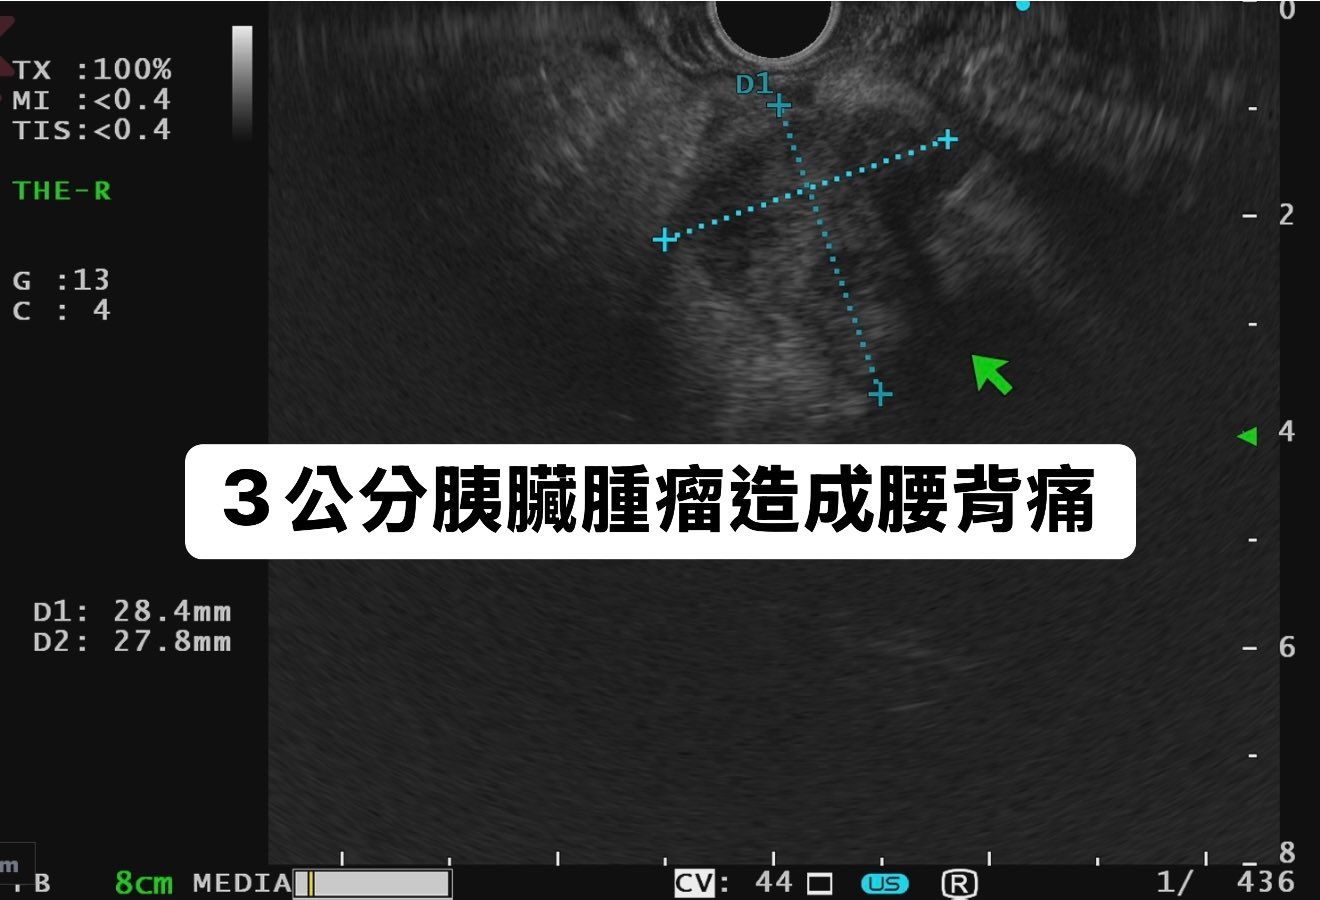

可能是 X 光和顯示的文字是「 TX :100% MI :<0.4 TIS: TIS:<0.4 4 THE-R THE R G G:13 :13 c C:4 4 D1: 28 28.4mm D1:28.4mm 4mm D2: 27 27.8mm 8mm 3公分膜臟腫瘤造成腰背痛 B 8cm MEDIA 'CV: 44 US R 8 436 」的圖像

然而,對方形容左腰和背部最近也有痠痛,對此林相宏稱不要永遠以為上腹痛都是胃部問題,尤其連帶背痛,要小心是胰臟或膽的問題。幸家屬有警覺性,趕緊帶該婦人接受檢查,林相宏隨即安排她接受胃鏡、大腸鏡、胰臟內視鏡超聲波檢查,結果在胰臟尾部、靠近背後的地方發現一個3厘米的胰臟癌,馬上安排手術治療。